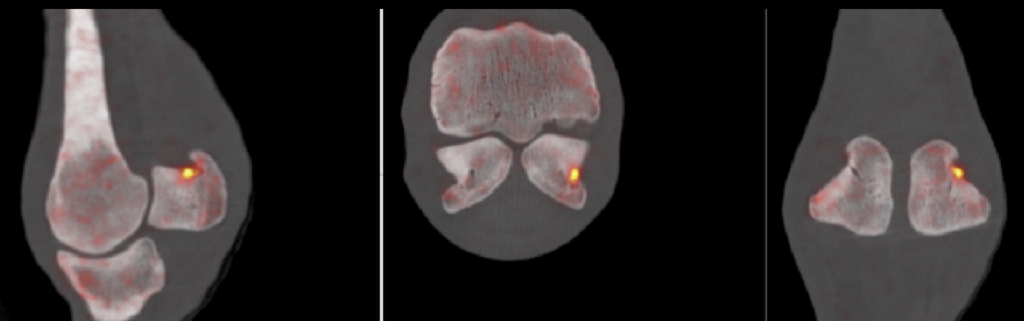

PETCT: PET is the most recent advance in diagnostic imaging. It is being developed in California and, when combined with CT, provides information on bone activity and structure. In these 3 images of the same fetlock from different aspects, the orange spo

On the first day of the workshop an expert panel discussed how diagnostic imaging prior to racing can contribute to risk reduction. At the current time, radiography is the most widely available tool used to identify tiny fractures which will heal effectively, providing exercise is reduced. Excitingly, technological progress in advanced imaging such as standing MRI, standing CT and PET scanning, have the potential to identify pathology even earlier. At the workshop, the expert panel reviewed existing knowledge and discussed how to generate the research evidence, which is essential if these novel technologies are to gain a place in effective pre-race risk assessment programmes.